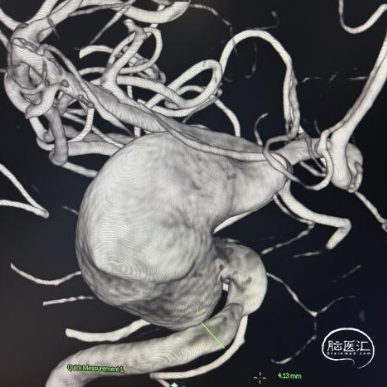

术前影像

脑动脉DSA提示右侧颈内动脉虹吸段巨大动脉瘤。

右侧虹吸段载瘤动脉近端直径为4.13mm,瘤体最宽径为24.2mm,动脉瘤流入、流出道均显示明显迂曲,近端载瘤动脉也有迂曲。病变范围约32mm。